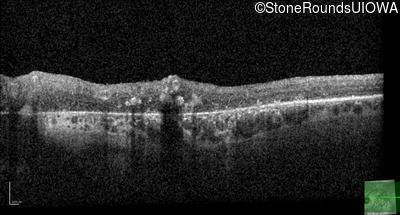

Cone-Rod Dystrophy (IA1b)

Age at visit: 58 years

This 58 year old woman first noticed a gap in the vision of her left eye at age 46.

Diagnosis & molecular findings

Disease Gene Allele 1 variant(s) Allele 2 variant(s) Inheritance mode

Cone-Rod Dystrophy CRB1 Cys948Tyr (T)GT>(T)AT Asp165 del9cagGATGGAATT AR